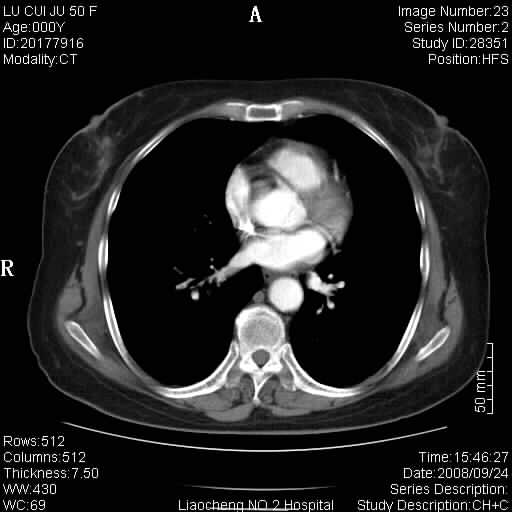

标题: CT15870:F50Y,纵膈占位,是不是胸腺瘤,请各位高手讨论。

临床表现为重症肌无力;ct增强扫描可见前纵膈胸腺部位弥漫性簇状软组织节结灶,不知道是不是胸腺瘤,请各位高手讨论。

胸腺组织残留

为未退化胸腺